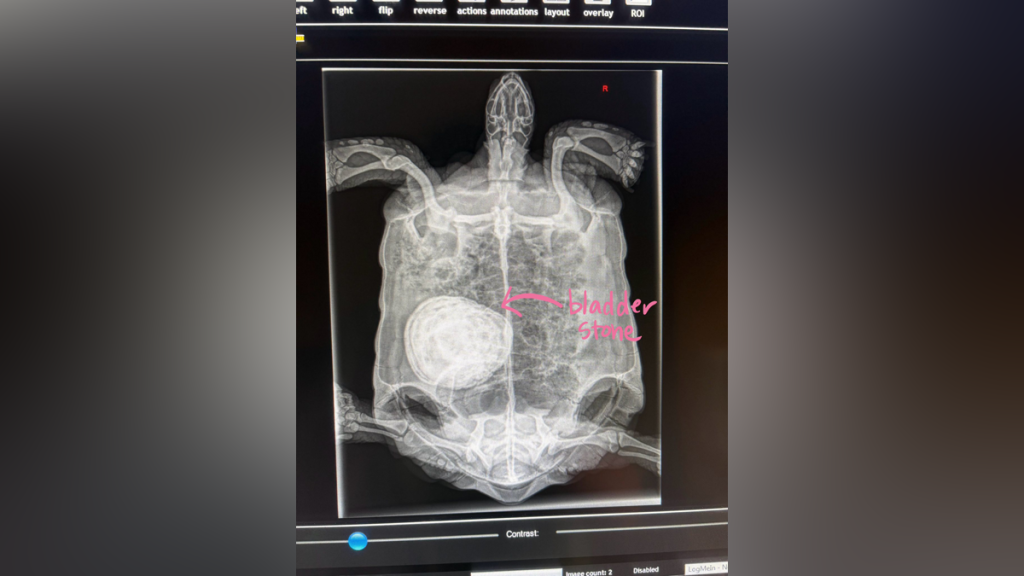

Baseball-sized stone removed from tortoise by NE Wildlife Center

A turtle is feeling relief after assistance from the New England Wildlife Center. Earlier tis week, veterinarians with the center removed a one pound stoneRead More